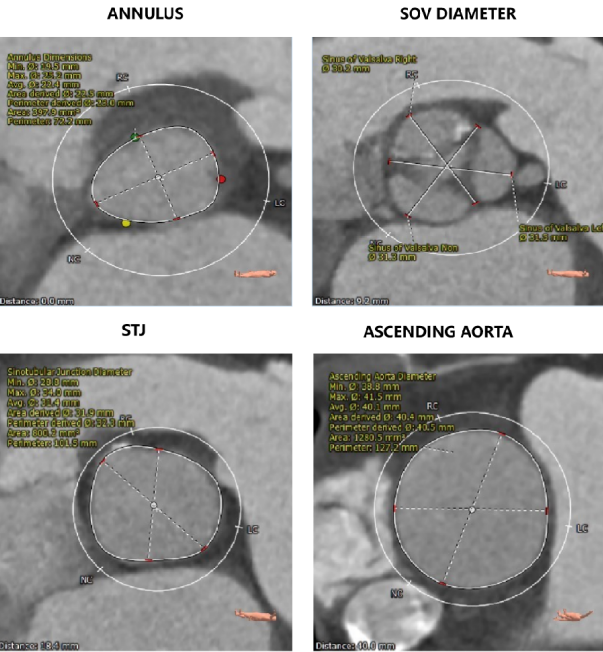

主动脉根部评估

CT数据显示该患者为三叶三窦式主动脉瓣。

左冠开口高度11.0mm,右冠开口高度17.9mm,左冠高度较低,根据瓦氏窦内径和瓣叶长度综合判断,左冠存在一定堵塞风险;左室腔增大,心室壁未见明显增厚。